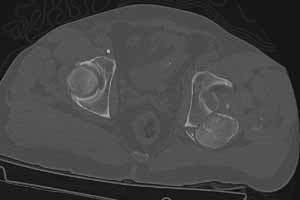

49 year old male, active speedskater, one year after MVC with multiple trauma and mild traumatic brain injury. Pipkin type IV fracture of the left hip. Same day ORIF through KL approach. No heterotopic ossification "prophylaxis". Day 7 wound revision for hematoma. Full weightbearing after 3 months. Full recovery except left hip function due to early severe HO. Function after one year: fixed ankylosis in 40 degrees flexion, 10 degrees exorotation. Patient frequently asks for attempt to improve hip function.

Post Op 1 year - Click to Magnify

Use the CT scan to direct your exposure for excision ... operate wherever the bone is ... sometimes it forms remote from your initial surgery site and demands a separate exposure.

A 3D CT helps define the margins and direct the exposure(s).

Question 3: Approach?

For excision of Class IV HO and sparing the femoral head if that remains an option I would say that based on your current CT scan that a dual approach tactic would be necessary - Kocher and Modified Smith Peterson. Position in true lateral for KL approach and can convert to semi-lateral for SP. Through either one could perform the Arthroplasty if head/cartilage viability was questioned on intraop evaluation. Post OP irradiation-our team prescribes single dose 750 mRad on post op day #1. Followed by indomethacin and possibly diphosphonates as adjunct with head salvage procedure being performed.